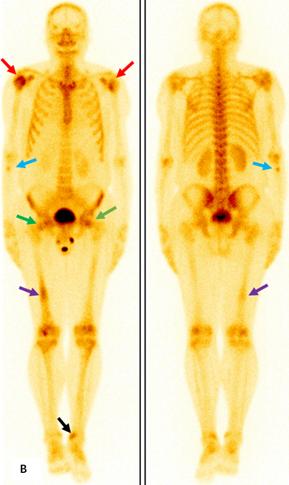

前列腺M(fèi)RI示:前列腺移行帶結(jié)節(jié)狀異常信號(hào),建議穿刺活檢;前列腺增生,PI-RADS2;雙側(cè)股骨頭信號(hào)異常,不排除轉(zhuǎn)移瘤(圖A)。為評(píng)估骨轉(zhuǎn)移情況遂行ECT全身骨顯像檢查,示:雙側(cè)肱骨頭、雙側(cè)股骨頭、右側(cè)前臂上段、右側(cè)股骨中下段代謝異常增強(qiáng)(圖B)。骨顯像不符合前列腺癌骨轉(zhuǎn)移典型表現(xiàn),同時(shí)結(jié)合患者胸部CT(圖C)平掃示右側(cè)腋窩多發(fā)淋巴結(jié)腫大,生化檢查示乳酸脫氫酶620U/L(97-270),懷疑系血液系統(tǒng)腫瘤,建議患者行PET/CT檢查。PET/CT示:右側(cè)腦室內(nèi)高密度灶,多發(fā)FDG代謝增高淋巴結(jié)及多發(fā)骨骼/骨髓FDG代謝增高灶,考慮淋巴瘤(圖D)。

ECT全身骨顯像示雙側(cè)肱骨頭(紅箭)、雙側(cè)股骨頭(綠箭)、右側(cè)前臂上段(藍(lán)箭)、右側(cè)股骨中下段(紫箭)、左側(cè)脛骨下端(黑箭)代謝異常增強(qiáng)。